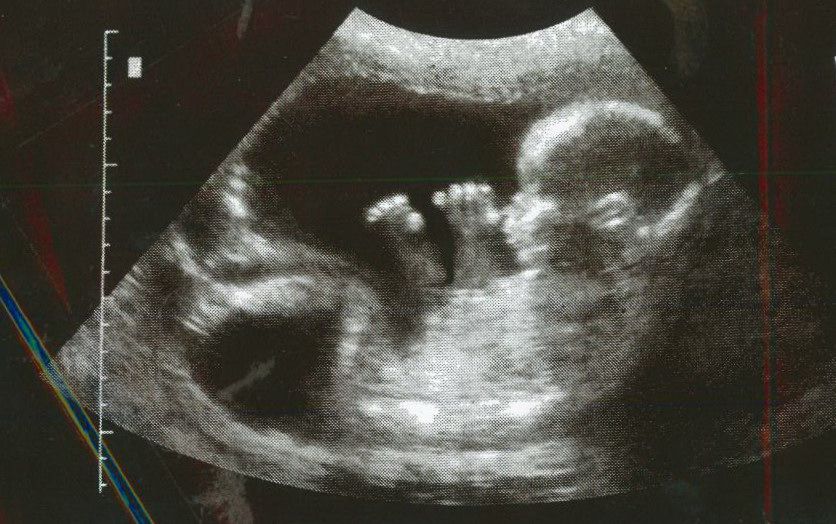

I can’t help but think this is still appropriate today, albeit for entirely different reasons. When a woman finds out she’s carrying a child, perhaps one that was far from planned, I imagine that a crippling fear is the first thing to surface. The same goes for a young father–the thought of life being forever changed is often the scariest thing that person has ever encountered. I can speak from experience, having nearly had to deal with it myself at 18.

The natural instinct anymore is, “How can I get rid of this?” and sadly, with abortion being as readily available–even encouraged–as it ever has been, the short-term solution is the one that’s picked nearly 1,000 times a day.

Though it’s substantially more difficult to endure, there is another, better way to wrestle with the fear that accompanies an unintended pregnancy:

Let your baby be born, then love the child fiercely.